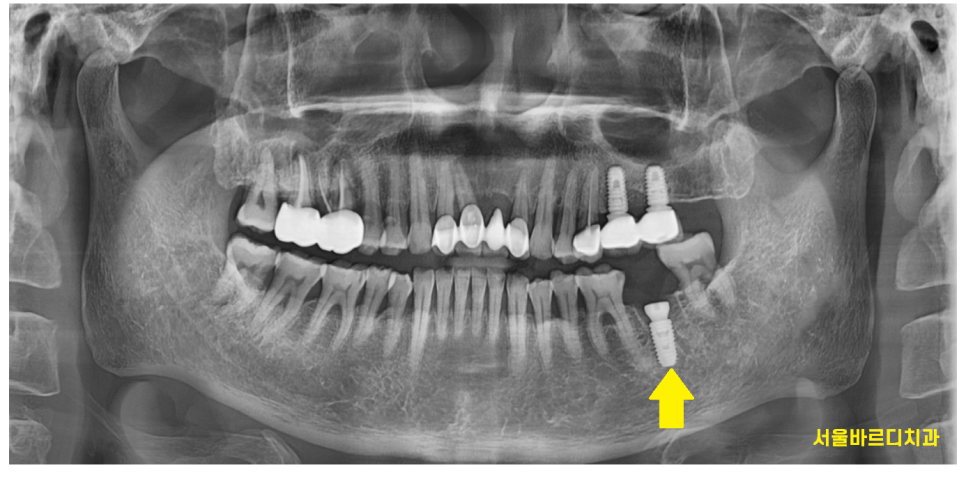

231030

천호동 치과 임플란트 수술 사진입니다.

양 옆 치아와의 간격

임플란트 각도

식립 높이

맘에 듭니다.